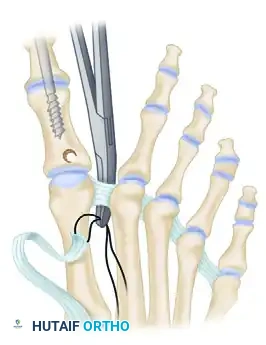

Step 4: IP Joint Fixation (Shives and Johnson Technique)

Rigid internal fixation is paramount for a successful arthrodesis. The use of a 4.0-mm cancellous lag screw, as advocated by Shives and Johnson, provides excellent compression and rotational stability.

- Retrograde Drilling: Drill a 2.0-mm diameter hole longitudinally in a retrograde manner starting at the center of the denuded articular surface of the distal phalanx.

- The drill bit should exit the skin at a point exactly 5 mm plantar to the tip of the nail in the midline of the toe.

- Antegrade Drilling: Appose the denuded articular surfaces of the proximal and distal phalanges in neutral alignment. Insert the drill bit distally at the tip of the toe (through the previously created exit hole) and advance it proximally.

- Follow the previously placed retrograde hole, cross the IP joint, and drill into the base of the proximal phalanx, advancing down the center of its medullary canal.

- Overdrilling and Tapping: To achieve a true lag effect, overdrill the distal phalanx (the near cortex) with a 2.7-mm drill bit to create a gliding hole. Tap the entire drill path with a 3.5-mm tap to prepare for the cancellous screw.

- Screw Insertion: Following the drill path in a proximal direction, insert a 4.0-mm partially threaded cancellous bone screw.

- As the screw head engages the distal phalanx, the lag effect will produce robust compression across the arthrodesis site, ensuring firm fixation.

Step 5: EHL Tendon Routing and Transfer

With the IP joint securely fused, attention is turned to the dynamic correction of the MTP joint. The goal is to route the EHL tendon to act as a lateral collateral ligament substitute and a plantarflexor.

- Identify the deep transverse metatarsal ligament in the first web space.

- Pass the mobilized EHL tendon plantar to the deep transverse metatarsal ligament. This critical step changes the vector of the EHL pull from dorsal-medial to plantar-lateral.

- Route the tendon dorsally to the base of the proximal phalanx.

- Prepare a drill hole through the base of the proximal phalanx from lateral to medial. Pass the EHL tendon through this osseous tunnel.

- Apply tension to the EHL tendon while holding the MTP joint in approximately 10 to 15 degrees of extension and neutral coronal alignment (correcting the varus).

- Suture the tendon back onto itself using non-absorbable braided suture (e.g., #2-0 FiberWire or Ethibond) to secure the transfer under appropriate physiological tension.